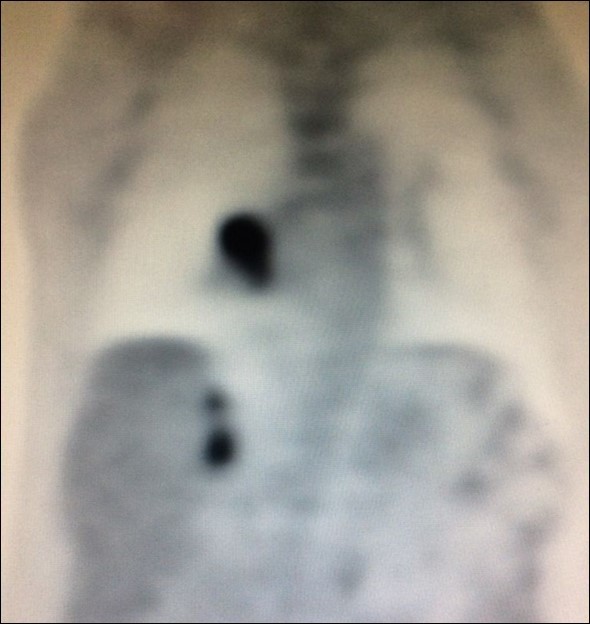

Adrenal biopsies (Figure 3) before adrenalectomy is useful in order to identify the nature of the lesion10,11,12. Even with fine-needle aspirate is possible a diagnosis and also a successful molecular testing by next-generation sequencing in order to the identification of pathogenic alterations linked to available or developing targeted therapies30.

Figure 3.Right adrenal needle biopsy (arrow)

There is limited understanding of the efficacy of surgical resection because of low incidence of isolated adrenal metastasis in patients with stage IV NSCLC. Some series showed that the time from diagnosis of primary lung cancer diagnosis of adrenal metastasis - disease-free interval (DFI) – is a prognostic factor6. Synchronous metastases (Figure 4), defined as a DFI of 6 months or less, has been associated with a poor prognosis.

Figure 4.PET CT showing simultaneous uptake on right lung mass and 2 ipsilateral adrenal nodules.